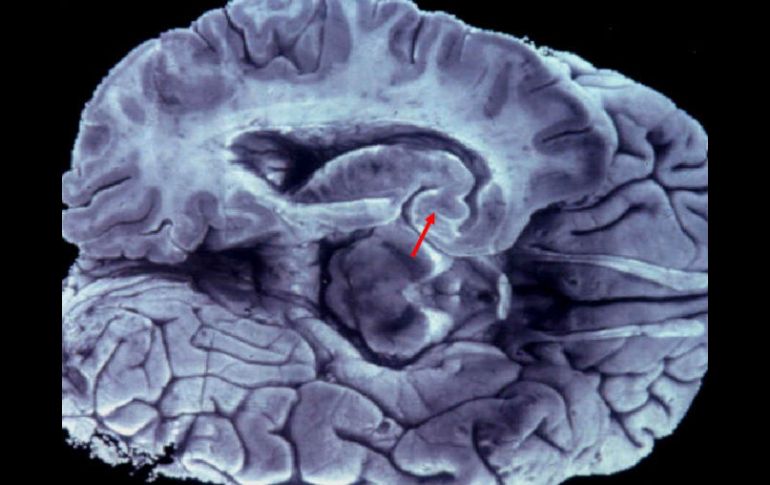

Tecnología | Los investigadores creen que podrían estar relacionadas con enfermedades metabólicas Identifican familia de seis genes claves en funcionamiento de cerebro Los científicos comprobaron que estos genes se encuentran sólo en los mamíferos más evolucionados Por: NTX 9 de mayo de 2012 - 13:41 hs Muchas enfermedades neurológicas se deben a alteraciones de genes. ARCHIVO / MADRID, ESPAÑA (09/MAY/2012).- Un equipo del Instituto de Investigación Biomédica (IRB Barcelona), encabezado por el científico Eduardo Soriano, identificó una nueva familia de seis genes cuya función es regular el movimiento y posición de las mitocondrias en las neuronas. Afirmó que "hemos encontrado un complejo de genes nuevos que están altamente expresados en el sistema nervioso y tienen una función muy concreta en un proceso que biológicamente es muy importante para la actividad del sistema nervioso y su viabilidad". El estudio está publicado en la revista "Nature Communications", indicó en un comunicado el IRB de Barcelona, noreste español. Muchas enfermedades neurológicas que incluyen el Parkinson o varias versiones del mal de Charcot-Marie-Tooth se deben a alteraciones de genes que regulan el transporte de estos orgánulos, que proporcionan la energía necesaria para el funcionamiento de las células, señaló. Los científicos comprobaron a través de análisis genómicos comparados que estos genes se encuentran sólo en los mamíferos más evolucionados, los denominados euterios, con fecundación y desarrollo internos. "El hallazgo indica la importancia de la biología de las mitocondrias. Cuando el cerebro evolucionó en volumen, función y estructura, el proceso de transporte de mitocondrias también se hizo más complejo y probablemente requirió mecanismos adicionales de control", explicó Soriano. El catedrático del Departamento de Genética de la UB y miembro del Instituto de Biomedicina de la UB (IBUB), Jordi Garcia-Fernández, colaborador en el estudio, también habló del mismo. Resaltó que dado el origen del clúster génico, en la transición entre mamíferos primitivos, como los marsupiales (canguros) y el resto de mamíferos placentarios, es tentador lanzar la hipótesis de que su origen esté ligado al incremento en complejidad del córtex cerebral en el linaje que lleva hasta el hombre. Subrayó que para que el cerebro funcione correctamente requiere una gran cantidad de energía, pero esta energía tiene que estar exquisitamente distribuida a lo largo y ancho de las neuronas, unas células que tienen ramificaciones que pueden llegar a ser de decenas de centímetros, desde el cerebro hasta las extremidades. Este complejo de genes descritos ahora forman parte de la maquinaria de "ruedas" de las mitocondrias y regulan la localización que deben tener en cada célula según las necesidades energéticas que ésta tenga. Al respecto, Soriano expuso que "serían como un punto de control más en el tráfico de mitocondrias en las células e interaccionan con las proteínas mayores asociadas al control del transporte mitocondrial". Otra característica destacada de este nuevo set de proteínas es que se encuentran tanto en las mitocondrias, cuya función ya se ha descrito, como en el núcleo celular, donde se desconoce la función. "Es posible que también estén involucradas en la regulación de expresión de genes pero lo estamos investigando", dijo. Además de su potencial implicación en patologías del cerebro, los investigadores creen que podrían estar relacionadas con enfermedades metabólicas y cáncer. Temas Ciencia Descubrimientos ciencia Cerebro Lee También Julieta Fierro será homenajeada en la FIL Nobel de Química premia el desarrollo de estructuras metal-orgánicas Nobel de Física para Clarke, Devoret y Martinis por descubrimiento sobre fenómenos cuánticos Nobel de Medicina premia investigación sobre el control del sistema inmunitario Recibe las últimas noticias en tu e-mail Todo lo que necesitas saber para comenzar tu día Registrarse implica aceptar los Términos y Condiciones